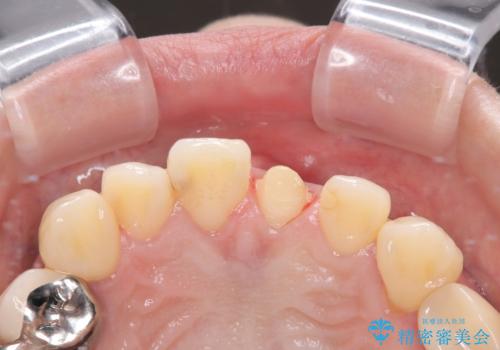

- 以前保険診療で行った前歯を自然できれいなセラミックにしたいと来院された患者様です。

古い材料と虫歯を除去して、土台の形を整え、より自然なオールセラミッククラウンにすることとしました。